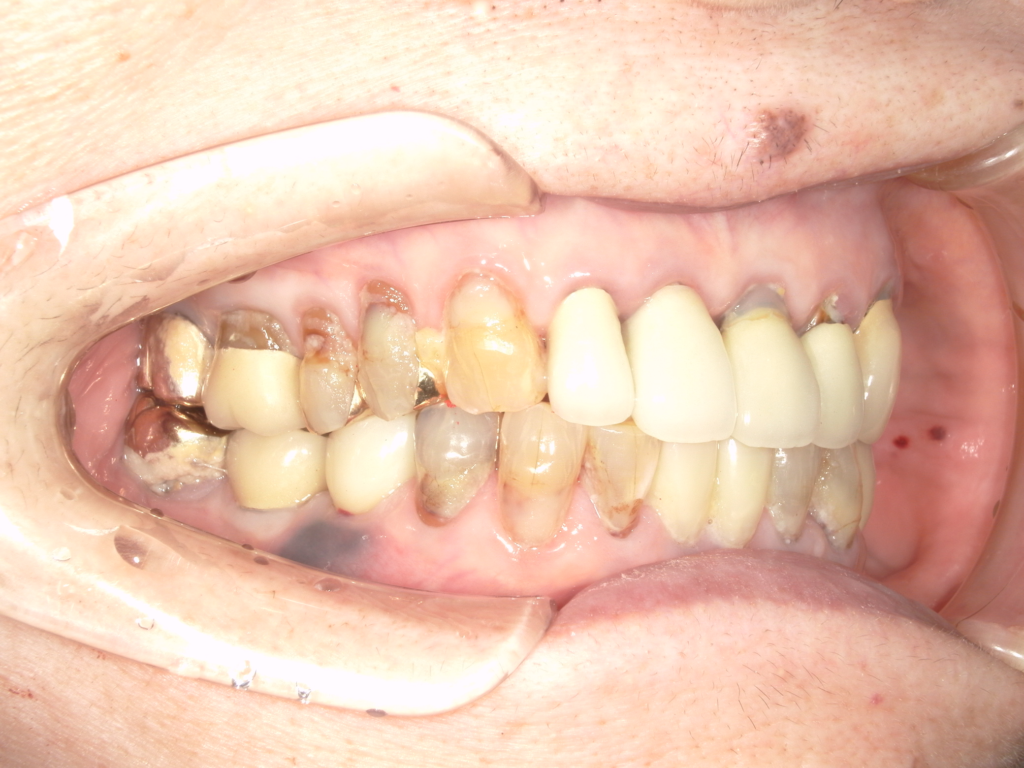

Y様インプラント実例 #44

左の上下の奥歯をインプラントで治療しています。

左下の奥歯は歯を抜くのと同時にインプラントの埋め込みを行っています。

被せものは上下、セラミックスで作っています。

治療前

治療後